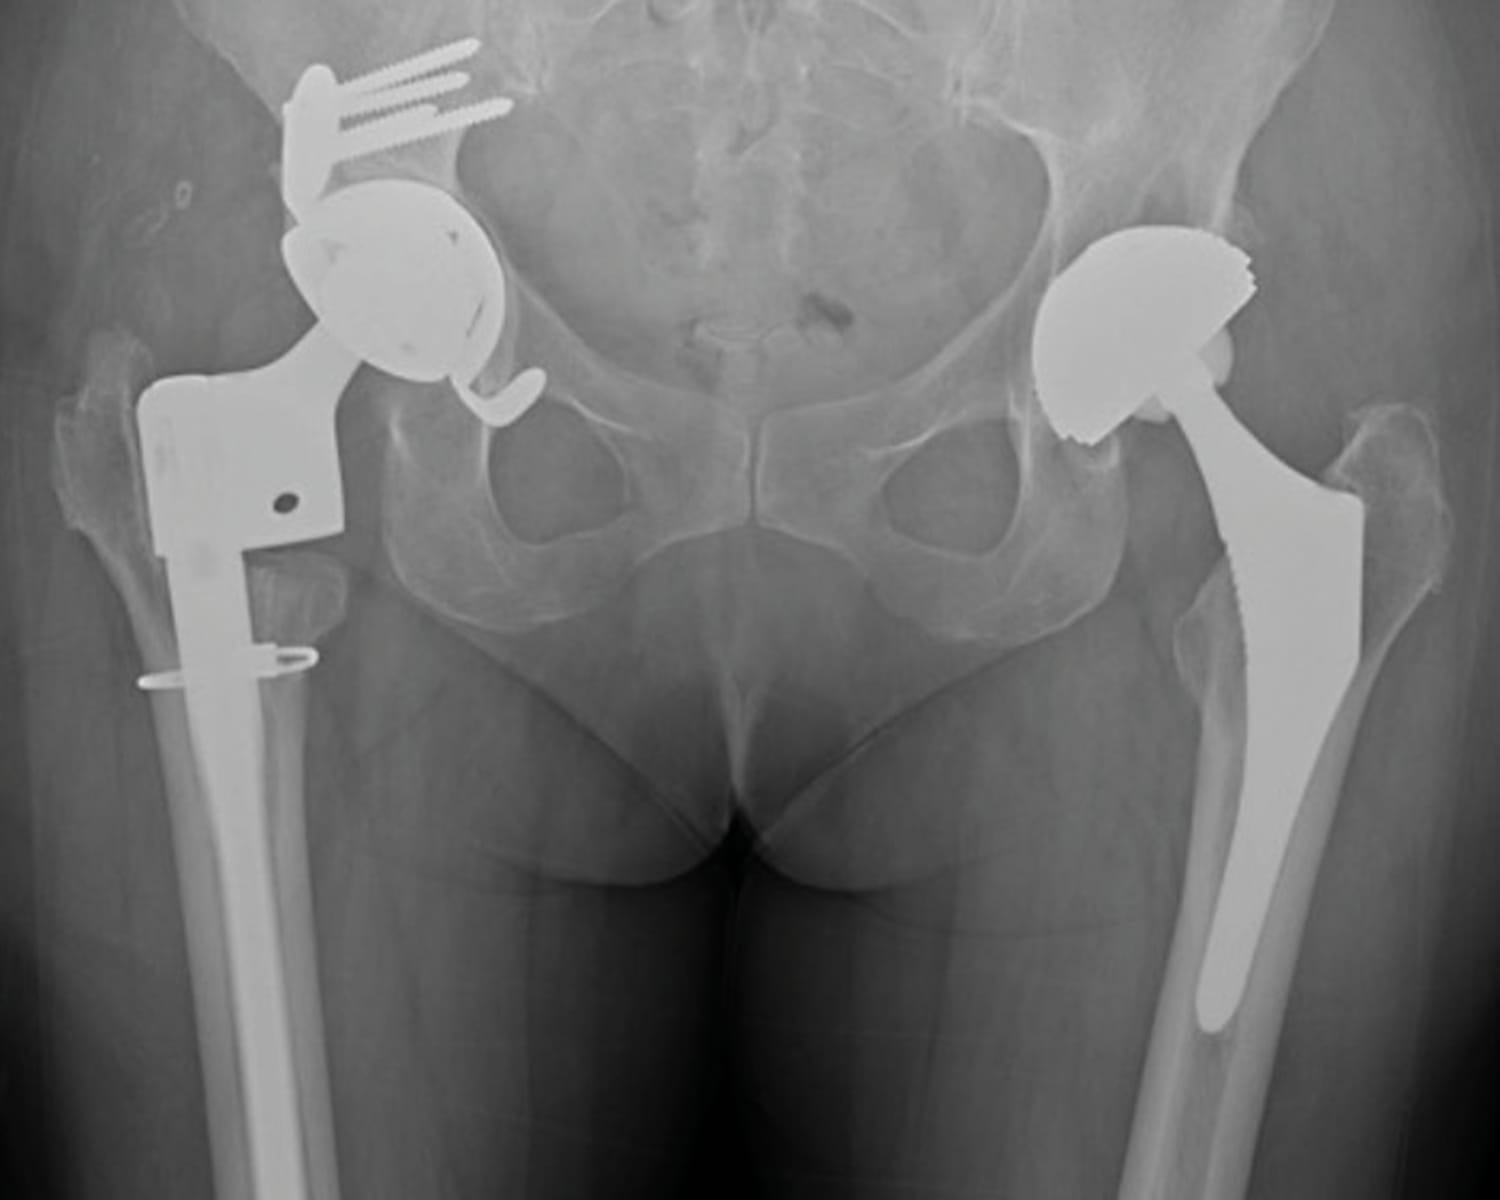

The clinical contributions in this issue address two principal domains. Musculoskeletal infection is examined through a case report on septic arthritis of the native hip caused by Granulicatella adiacens, complemented by a literature review, and a case series investigating surgical options and outcomes in calcaneal osteomyelitis. The issue further addresses revision of total hip arthroplasty, presenting an epidemiological multicentre analysis of 963 patients in France alongside an evaluation of dual mobility systems as a reconstructive strategy in revision settings.